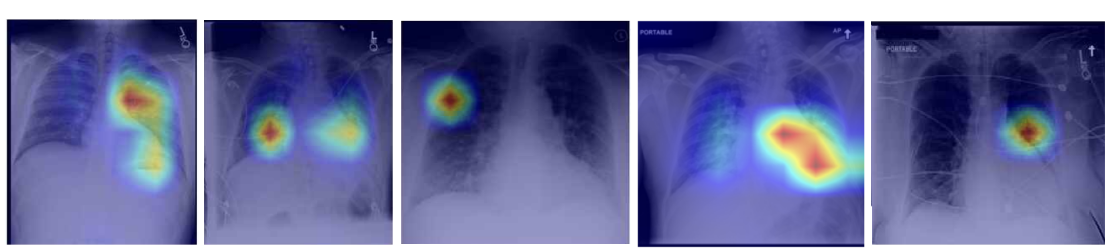

Figure 3 shows a qualitative comparison between MATEX and M2IB on the MS-CXR dataset. Each column depicts a clinical case, with MATEX heatmaps on the top row and M2IB results below, visualized as overlayed attribution maps on chest X-rays.

Figure 3 illustrates that MATEX offers several consistent improvements over M2IB. Across all evaluated cases, MATEX produces heatmaps with sharper localization and tighter alignment to pathological regions, enhancing anatomical coherence. In scenarios involving bilateral or multi-zone findings—such as lower lobe consolidation—MATEX accurately captures both affected zones while avoiding overspill, whereas M2IB often yields diffuse attention. Additionally, MATEX exhibits improved boundary adherence, particularly in cases of opacification, which enhances interpretability for clinical use. It also demonstrates reduced noise activation by limiting attribution to relevant structures, unlike M2IB, which sometimes highlights unrelated areas.

These improvements are attributable to MATEX’s ability to produce more anatomically precise and clinically aligned explanations. The framework effectively captures multi-region pathologies without spatial drift and maintains clear boundaries around relevant findings.